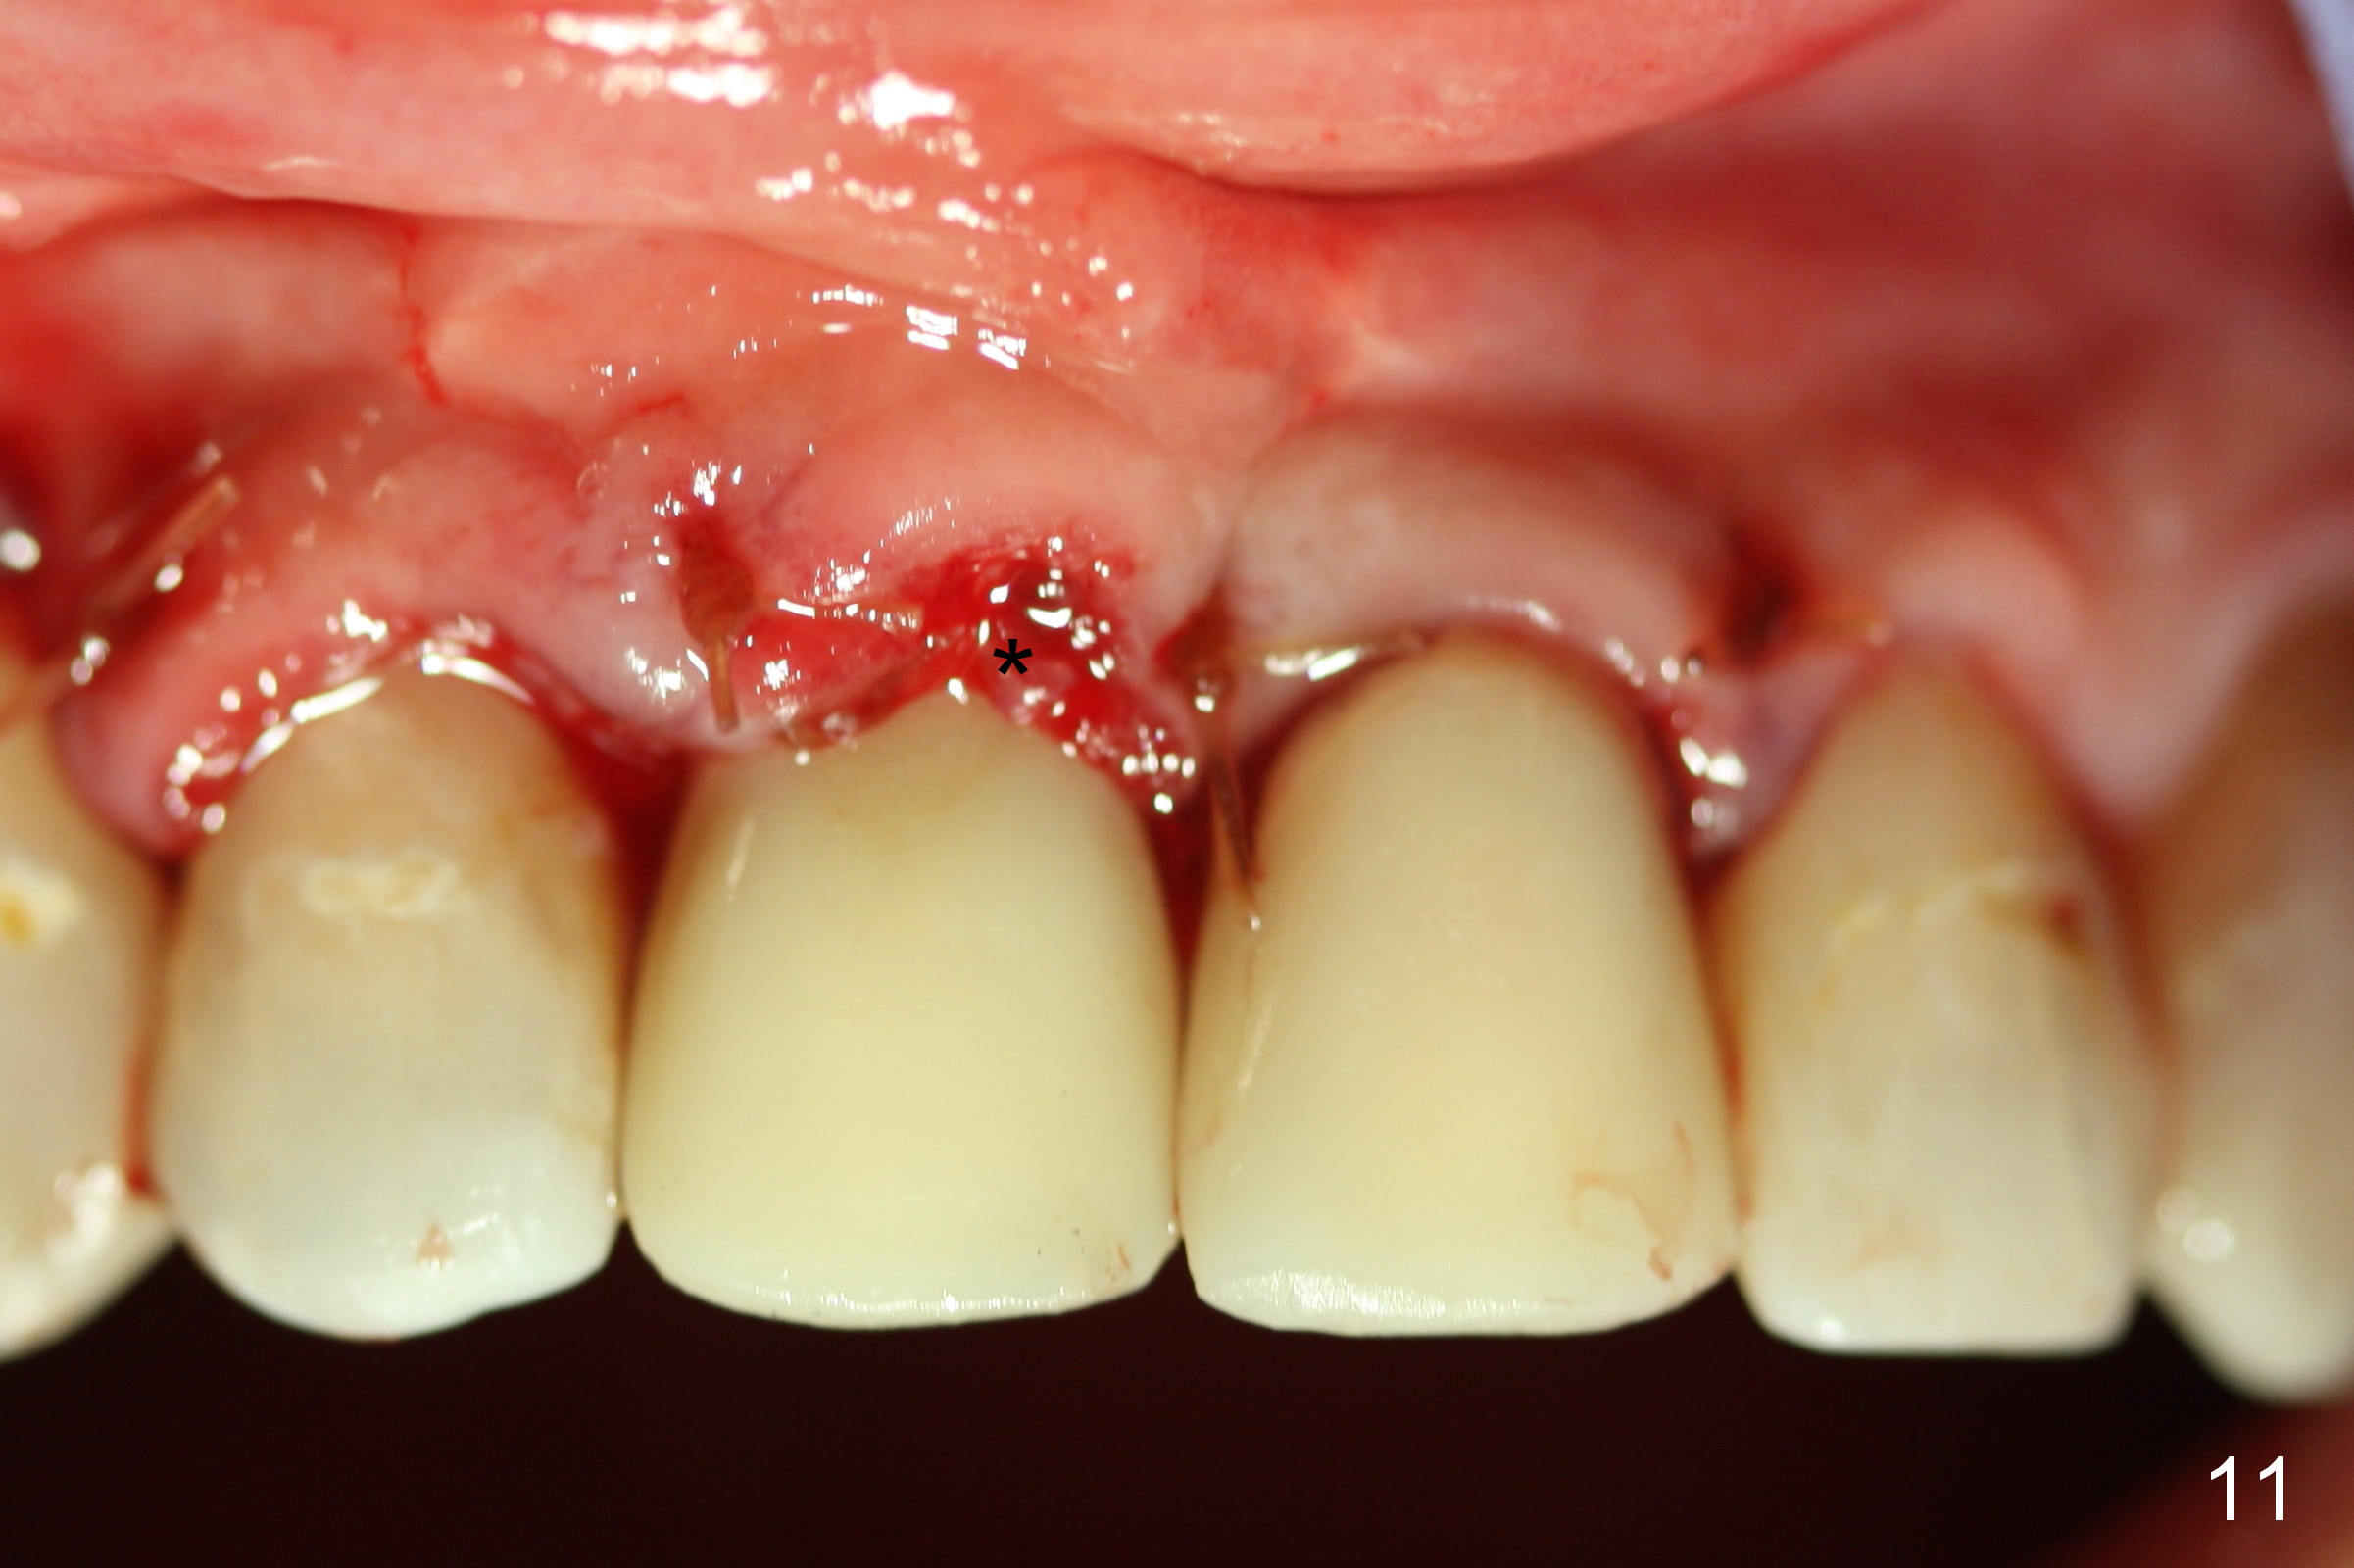

To correct the gingival margin associated with #8 implant, bone graft is needed.  Particulate graft may not stay in place. Chin graft is harvested.  Since the roots of the lower anterior teeth are long (Fig.8), the width of the chin graft is limited for direct screw fixation (Fig.9,10).  Titanium mesh is used for fixation of the graft.  Connective tissue graft from the palate is to increase bulk at the site of #8 (Fig.11 *).  There is no symptom or sign of infection 1 month postop (Fig.12,13).  Although there is alteration of sensation of the lower incisors, there is no apical radiolucency of them 4 months postop (Fig14).  There is no abnormality associated with the bone graft and Titanium mesh (Fig.15).